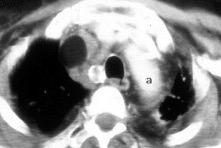

Triada de Garland

Ganglios paratraqueales derechos e hiliares bilaterales

95% de pacientes tienen ganglios hiliares bilaterales aislados o con afectación mediastínica (espec. paratraqueal derecho).

Criado E et al. Pulmonary sarcoidosis: typical and atypical manifestations at high-resolution CT with pathologic correlation. Radiographics. 2010